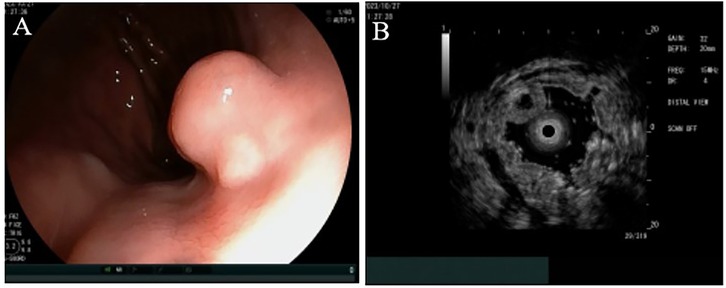

Upon examination, no pigmentation was observed in the oral cavity or on the lips. The patient's abdomen was flat and soft, without varicose veins on the abdominal wall. Vital signs such as respiratory rate and heart rate were within normal range, and there were no murmurs on auscultation of the heart and lungs. The physical examination and laboratory results upon admission did not reveal any abnormalities. Upper gastrointestinal endoscopy confirmed the presence of an SMT in the cardia, which exhibited no apparent erosion (see Figure 1A). Endoscopic ultrasonography indicated a heterogeneous tumor predominantly situated within the third (submucosal) layer (see Figure 1B). These observations raised the suspicion of a malignant neoplasm; however, a definitive diagnosis could not be established based solely on these findings. Consequently, it was deemed necessary to perform resection to obtain an accurate diagnosis and determine the most appropriate treatment. Given the challenges associated with conventional endoscopic mucosal resection (EMR) techniques, such as strip biopsy and EMR using a cap-fitted endoscope, we opted to utilize the ESD technique to achieve complete tumor resection in a single en bloc.

Figure 1. Endoscopic findings. (A) A hemispherical smooth submucosal mass was observed on white light endoscopy. (B) Endoscopic ultrasonography showed a hypoechoic mass with uniform internal echo originating from the third (submucosal) layer.

GHIP is believed to arise from the infiltration of the mucosa through the muscularis layer, as well as from mucosal crevices or defects resulting from recurrent erosion (10). Typically, GHIP is identified as an isolated submucosal mass during endoscopic procedures (11). An endoscopic evaluation conducted by Dohi indicated that the lesion was enveloped by a normal mucous membrane, characterized by a distinct irregular depression at its apex (12). In a case documented by Takuma Okamura, the use of magnification endoscopy and narrow-band imaging revealed a reddened area surrounding the depression, along with an irregular arrangement of villi and pits, lacking a clear demarcation (13). Consequently, diagnosing GHIP based solely on endoscopic findings presents challenges. Endoscopic ultrasonography typically demonstrates heterogeneous tumors with cystic components. In the case reported by Okamura, endoscopic ultrasonography identified a nonuniform tumor with cystic areas situated within the third layer (13). Additionally, the case presented by Moyu Dohi exhibited a heterogeneous tumor originating from the second layer, characterized by small cystic hypoechoic spots observed via ultrasound endoscopy (12). In this instance, endoscopic ultrasonography confirmed the presence of a heterogeneous tumor, predominantly located within the third (submucosal) layer.